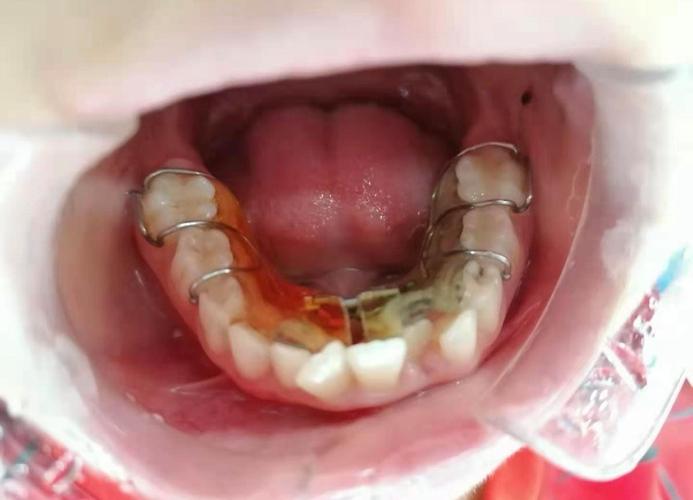

正畸后牙齿斜的首要原因与“保持器”密切相关,牙齿移动后,牙槽骨需要时间重建,牙周组织(如牙龈、牙周膜)也需要时间适应新的位置,这个过程被称为“牙骨改建稳定期”,通常需要1-2年,若在此期间未严格佩戴保持器,牙齿可能会因周围肌肉(如舌肌、唇肌)的异常力量、咀嚼时的咬合干扰,或自身重力作用而逐渐移位,夜间不戴保持器,白天仅佩戴数小时,无法对抗夜间牙齿的自然漂移趋势,久而久之便会导致牙齿倾斜,保持器本身也存在损耗问题,如透明保持器因长期佩戴变松、钢丝保持器的钢丝变形等,无法有效固定牙齿,也会引发移位。

针对上述原因,解决正畸后牙齿斜问题需“对症下药”,若因保持器问题,首先需检查保持器是否贴合,若已变形或松脱,需及时重新制作,保持器需全天佩戴(除吃饭、刷牙外)至少6个月,之后过渡到夜间长期佩戴,甚至终身佩戴,对于牙周问题患者,需先进行牙周系统治疗(如洁治、刮治、牙周手术等),控制炎症,改善牙周环境,必要时结合牙周夹板固定松动牙齿,咬合干扰导致的牙齿斜,需进行咬合调整,如调磨过高牙尖、制作咬合板,或通过修复治疗(如牙冠、嵌体)恢复咬合平衡,生长发育因素引发的,需定期监测颌骨变化,必要时在成年后进行二次矫正,若矫正方案或执行存在缺陷,则可能通过隐形矫正或固定矫正进行精细调整,重新排齐牙齿并建立稳定咬合。